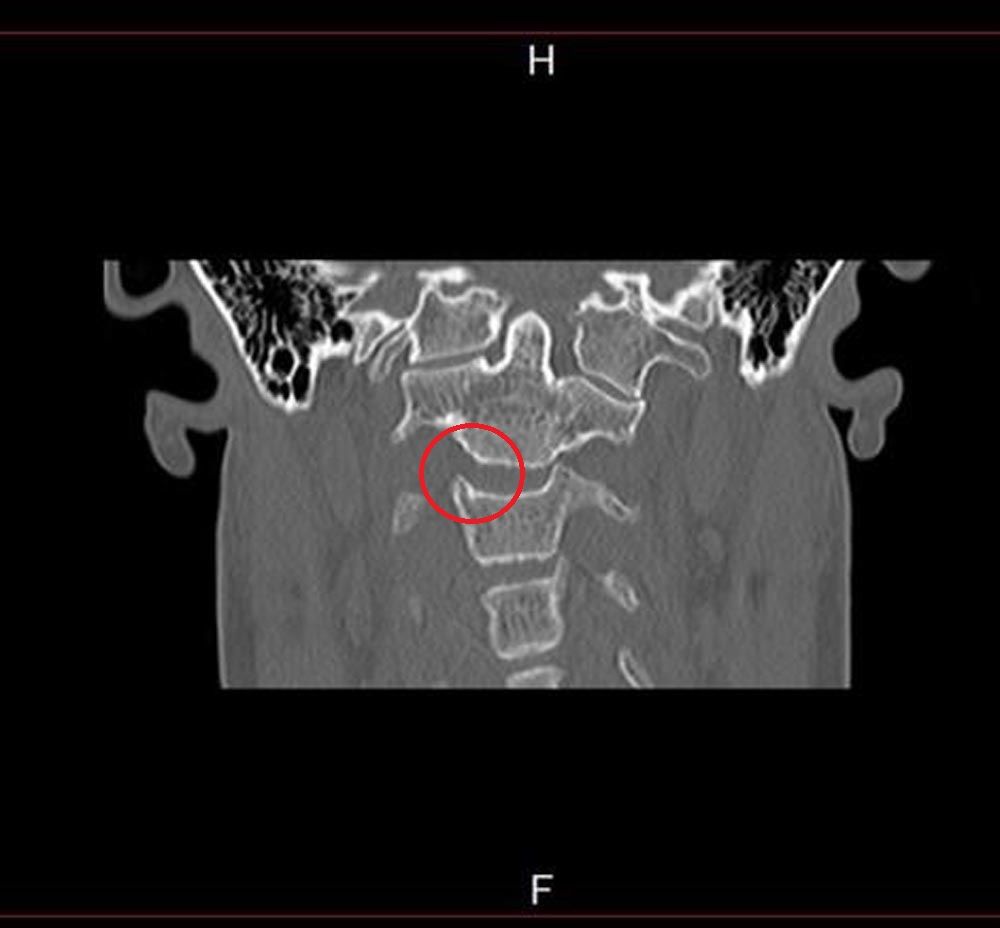

Diagnosed with atlantoaxial instability, resulting in excessive movement between the first and second vertebrae of the neck, which holds the skull in place, Rachel Pighills' spine partially dislocates each time she turns her head to the left, increasing her risk of paralysis.

“In May 2019 I spoke to a specialist based in Barcelona who said my case is severe and I'm at risk of internal decapitation. Turning to the left causes my cervical spine junction to partially dislocate and I could die instantly if it fully dislocates."

In June 2019 Rachel saw another neurologist, who diagnosed her with platybasia, a flattening of the skull base, and basilar invagination, an infolding of the base of the skull, which occurs when one of the vertebra migrates upwards.

Having assessed the MRI and carried out a detailed questionnaire, he added to her diagnosis atlantoaxial instability – where the vertebrae holding her skull in place become unstable and dislocated, hydrocephalus, which is an accumulation of cerebrospinal fluid within the brain, scoliosis, a curvature of the spine, and cervical medullary syndrome, which is caused by brain stem compression.

“I will have to have two operations. The first will remove the odontoid bone which is compressing my brain stem and the second a week later will fuse my skull and neck together," Rachel explained.